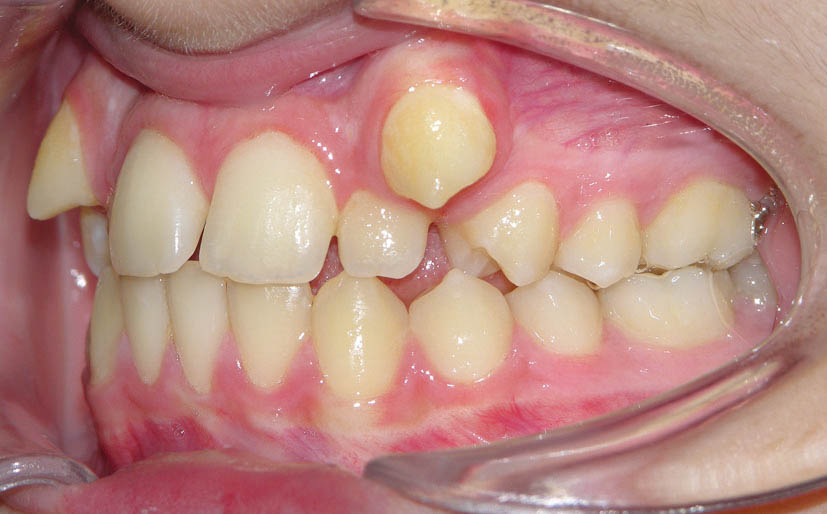

شکل 94-2: اکلوژن یک کاسپ کامل کلاسII در سمت راست

شکل 95-2: اکلوژن نیم کاسپ کلاسII در سمت چپ